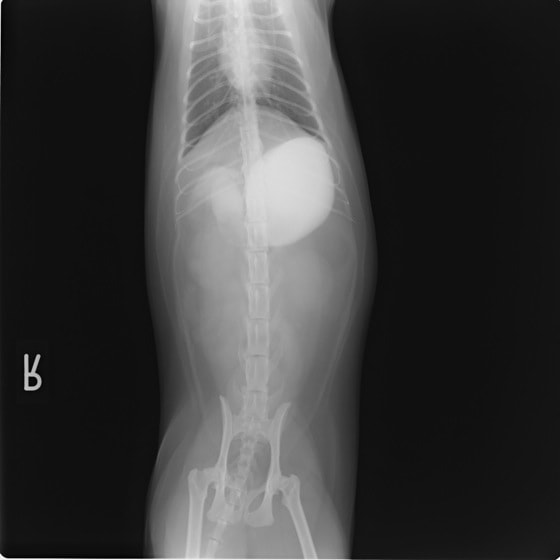

4歳 アメリカンショートヘアー

主訴:3日前から嘔吐が続き、食欲も落ちてきたのこと。

対症療法(症状に対する治療)に反応しないため、精査を実施。

一般血液検査:問題なし

単純レントゲン検査:胃内ガス陰影・腸内ガスが少量認められる。

嘔吐が改善しないため、消化管バリウム造影検査を実施。

以下、

消化管バリウム造影レントゲン

バリウム造影3時間経過するも、胃内からバリウム排泄なく同日内視鏡検査を実施。